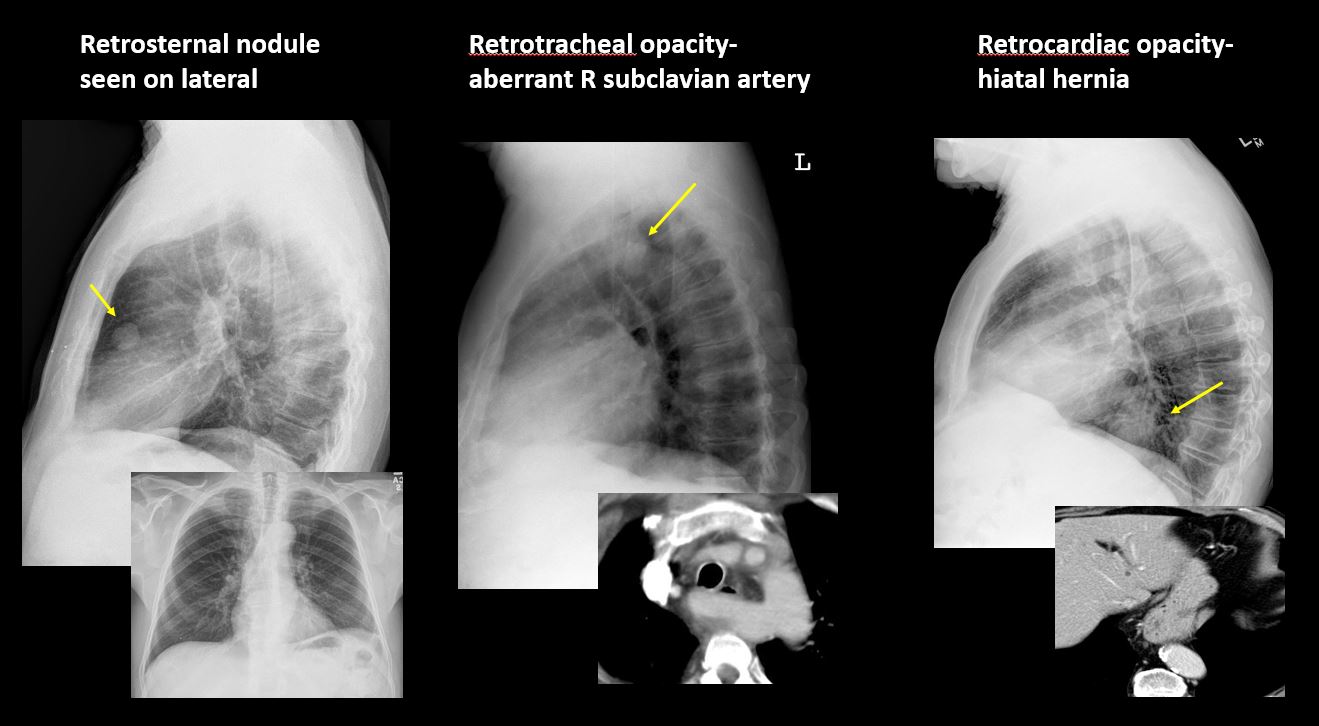

Section 1 Submit Findings Case322 Findings Technique The exam is expiratory, rotated, over or under penetrated, or limited by overlying structures or soft tissues, body habitus, patient positioning, or motion. Yes No Support Devices There is a vascular line or lines present in an abnormal location or otherwise abnormal. Yes No There are other devices such as a chest tube or pleural drain, feeding, NG, or gastrostomy tube, LVAD or pacemaker, vascular stents, cardiac valves, anesthesia catheter, VP shunt, neurostimulator, or other drains or tubes present that are in an abnormal position or are otherwise abnormal. Yes No Cardiomediastinum The superior mediastinum is abnormally widened considering the technique. Yes No There is abnormal shift of the mediastinum. Yes No There is a mass or other abnormal density in or overlying the mediastinum. Yes No There is an abnormality in the retrosternal, retrotracheal, or retrocardiac space on the lateral view. Yes No There is abnormal tracheal deviation or narrowing on the frontal and/or lateral view. Yes No There is pneumomediastinum and/or pneumopericardium. Yes No There is enlargement of the cardiac silhouette. Yes No The heart borders are abnormal. Yes No The right paratracheal stripe is thickened or enlarged. Yes No The azygoesophageal recess is displaced or otherwise obscured. Yes No Vasculature and Hila The aorta is dilated, tortuous, ectatic, calcified, or there is a focal contour abnormality. Yes No The central pulmonary arteries or hila are enlarged. Yes No The aorto-pulmonary window is convex or obscured by a mass, adenopathy, or vasculature. Yes No There is cephalization or haziness of the pulmonary vessels or congestion of the central pulmonary vasculature. Yes No Lungs The lungs are hyperinflated or underinflated generally or segmentally. Yes No There is focal, multifocal, or diffuse airspace disease, mass, opacity, or nodularity. Yes No There is focal or diffuse interstitial disease. Yes No There is focal or lobar atelectasis or total collapse of the lung. Yes No There is cavitary or cystic disease with or without air fluid levels or soft tissue nodularity. Yes No The position of the major and minor fissures is abnormal. Yes No The right or left hemidiaphragm is focally or diffusely obscured on the frontal and/or lateral view. Yes No There is elevation, depression, or contour abnormality of the right or left hemidiaphragm. Yes No Pleura There is focal or diffuse abnormality of the pleura or chest wall. Yes No There is a pleural effusion, blunting of the costophrenic angle, or posterior sulci. Yes No There is focal fluid in the fissures. Yes No There is asymmetric pleural thickening or capping of the apices. Yes No There is a pneumothorax, hydro/pneumothorax, or hemo/pneumothorax. Yes No Bones, Soft Tissues, Upper Abdomen The ribs, clavicles, shoulder, spine, or other visualized bones are abnormal. Yes No There is free air beneath the diaphragm. Yes No The bowel or organs of the upper abdomen are abnormal. Yes No There is subcutaneous emphysema, focal or diffuse soft tissue abnormality, radiopaque foreign body, or post-surgical change or hardware. Yes No